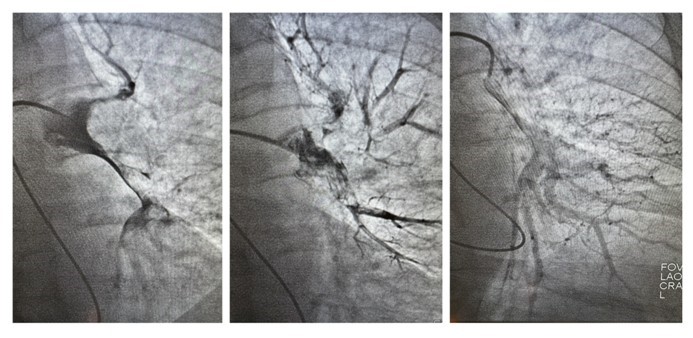

В больнице рассказывают, что одним из первых пациентов, на котором опробовали метод механической фрагментации тромба, стала 18-летняя девушка. В тот день утром ее выписали из другого стационара после операции на сломанном бедре, а вечером ее доставили в сосудистый центр больницы № 20 в тяжелом состоянии с симптомами тромбоэмболии. Врач-реаниматолог Владимир Радионов предложил попробовать разрушить тромб, который то перекрывал ток крови полностью, то частично открывал артерию. Для этого в легочную артерию под рентген-контролем ввели катетер, который обычно используется для оценки гемодинамики в отделах сердца. Девушка открыла глаза и стабилизировалась прямо на операционном столе и в скором времени была выписана из стационара со значительным улучшением.

Применяемая в 20-й больнице методика позволяет врачам через один прокол проникнуть в венозную сеть, откуда через сердце добраться до легочной артерии и ее ветви. Тромб разрушается на фрагменты. Это позволяет быстрее его растворить и избежать тяжелых осложнений за счет сокращения времени и снижения количества препарата. Врач наблюдает за процессом с помощью ангиографа. Для этого пациенту в кровь вводят контрастное вещество.

«Такая операция длится от получаса до двух часов, зависит от сложности доступа к тромбу, количества изгибов сосудистого русла, по которым нужно пройти, объема действий, которые нужно выполнить врачу-оператору. Есть тромбы очень податливые, которые буквально разрушаются на глазах. Есть такие, с которыми приходится изрядно повозиться. Как только удается разрушить тромб, в область тромбоза или непосредственно в тромбомассы вводится тромболитик, который завершает процесс» рассказали в минздраве.